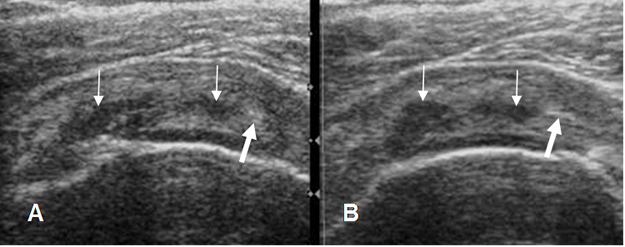

Fig 130. Tendinitis crónica del supraespinoso.

A y B: Ecografía coronal. Tendón del supraespinoso engrosado y con alteración de su ecogenicidad, con áreas hipoecoicas (Flechas delgadas) e hiperecoicas (Flechas gruesas), por inflamación crónica.